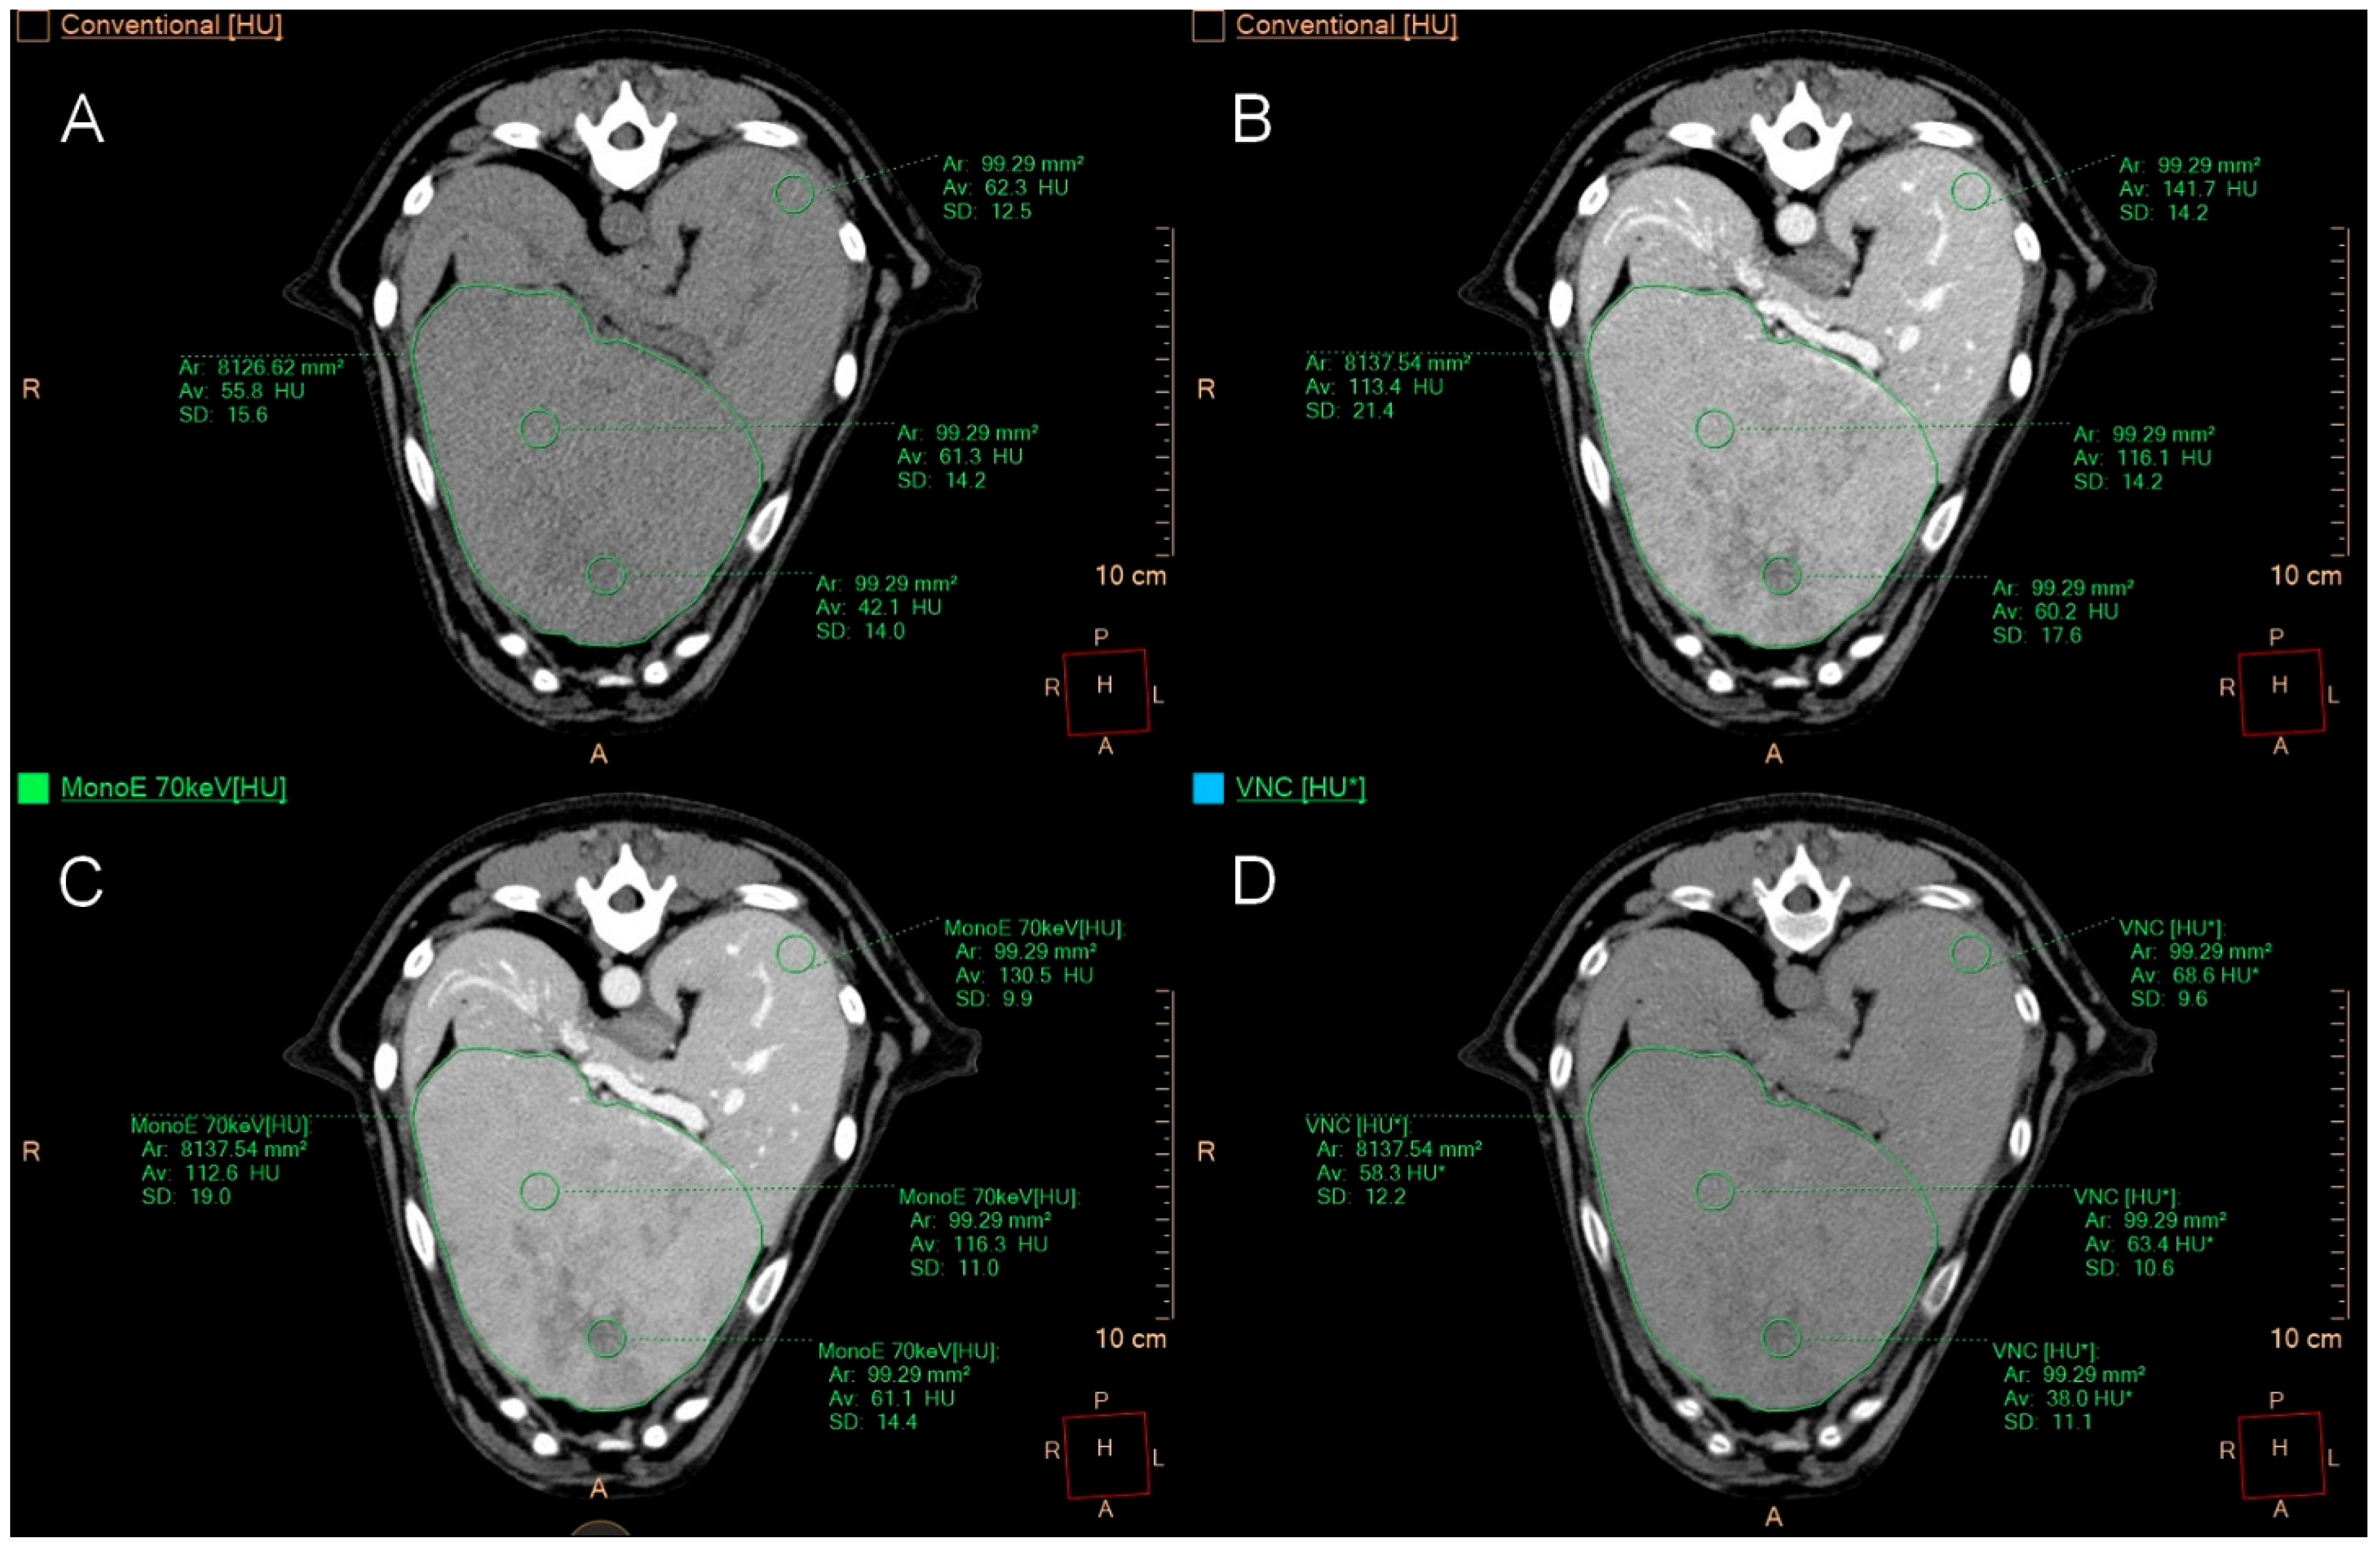

2.4. Quantitative Image Analysis

3.4. Quantitative Image Analysis